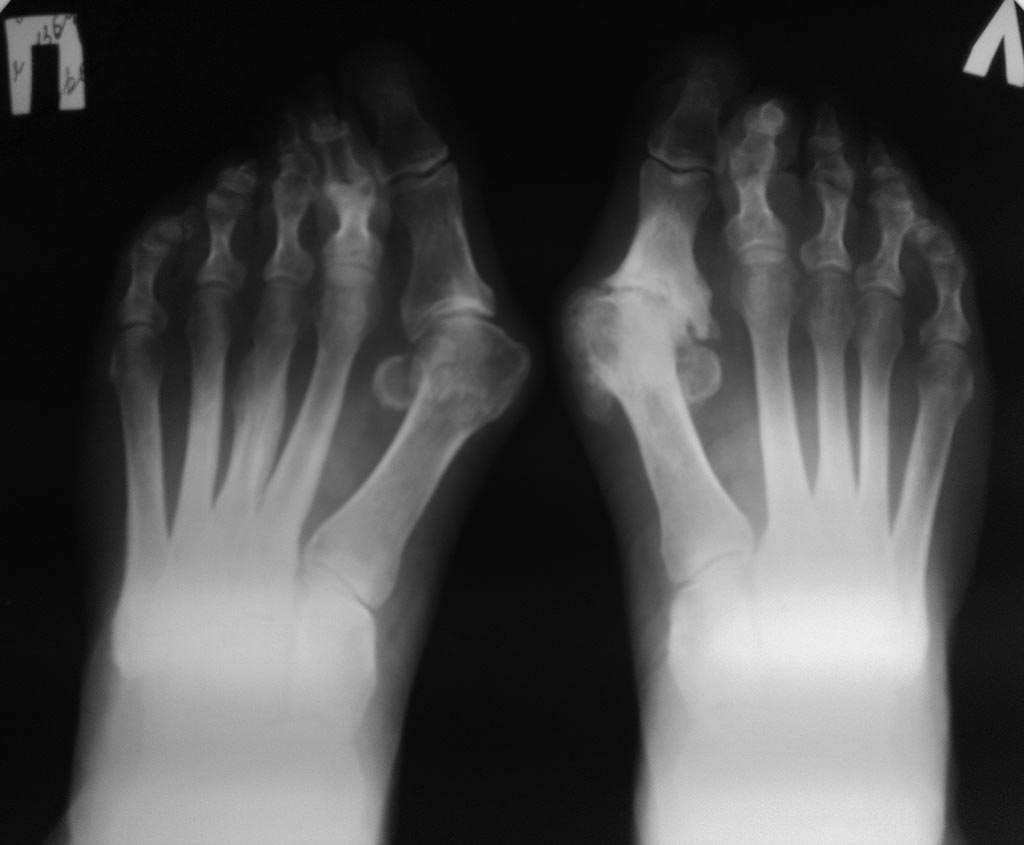

Женщина 60 лет,имеет деформацию пеереднего отдела обеих стоп в виде

Hallux valgus, молоткообразной деформации вторых пальцев, артроза первых

плюсне-фаланговых и других суставов. Каков может быть объем коррекции

стоп, с учетом артроза слева?